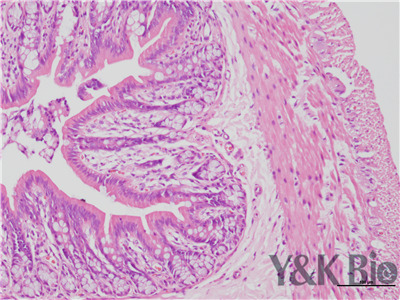

病理技术服务中HE染色法,学名苏木精-伊红染色,在法云南石蜡切片技术里是经常用的染色法之一。石蜡切片常用于观察正常细胞组织的形态结构,是病理学用以研究、观察及判断细胞组织形态变化的主要方法。苏木精染液是碱性的 ,主要使细胞核内的染色质与胞质内的核糖体着紫蓝色 ;伊红为酸性的染料 ,主要使细胞质和细胞外基质中的成分着红色。HE染色法是组织学、胚胎、病理学教学与科研中基本、使用广泛的技术方法。

HE染色中要注意细胞核的分化程度,注意苏木素和伊红的效价,及时更换染液,一般实验周期为15个工作日。